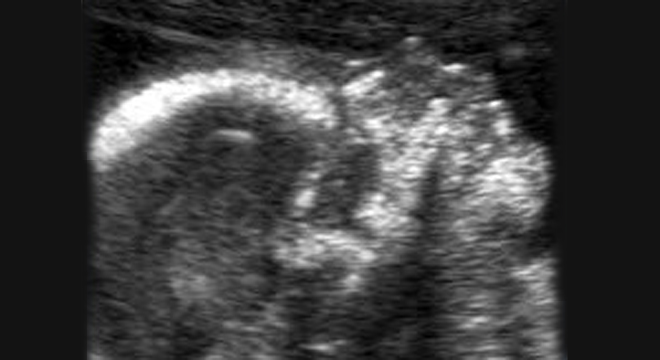

Lippen-Kiefer-Gaumenspalte: Ultraschalluntersuchung

Ab der 18.-20. Schwangerschaftswoche kann - im Rahmen einer Vorgeburts-Diagnostik - mittels Ultraschall eine Lippenspalte erkannt werden. Das genaue Ausmass der Gesichtsfehlbildungen wird allerdings erst nach der Geburt sichtbar.